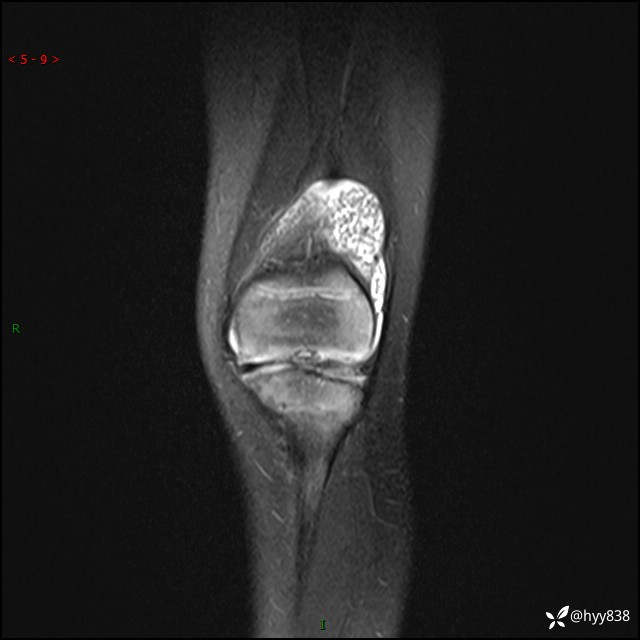

现病史:患儿1月前无明显诱因出现左下肢跛行,伴左膝关节红肿,无发热、咳嗽、恶心、呕吐等症,于当地医院就诊行X线片未提示异常,今至我院门诊就诊,门诊医师拟“跛行待查”收入院。 病后,患儿精神、食欲可,睡眠欠安,大小便通畅,体力体重无明显下降。

左膝MRI平扫